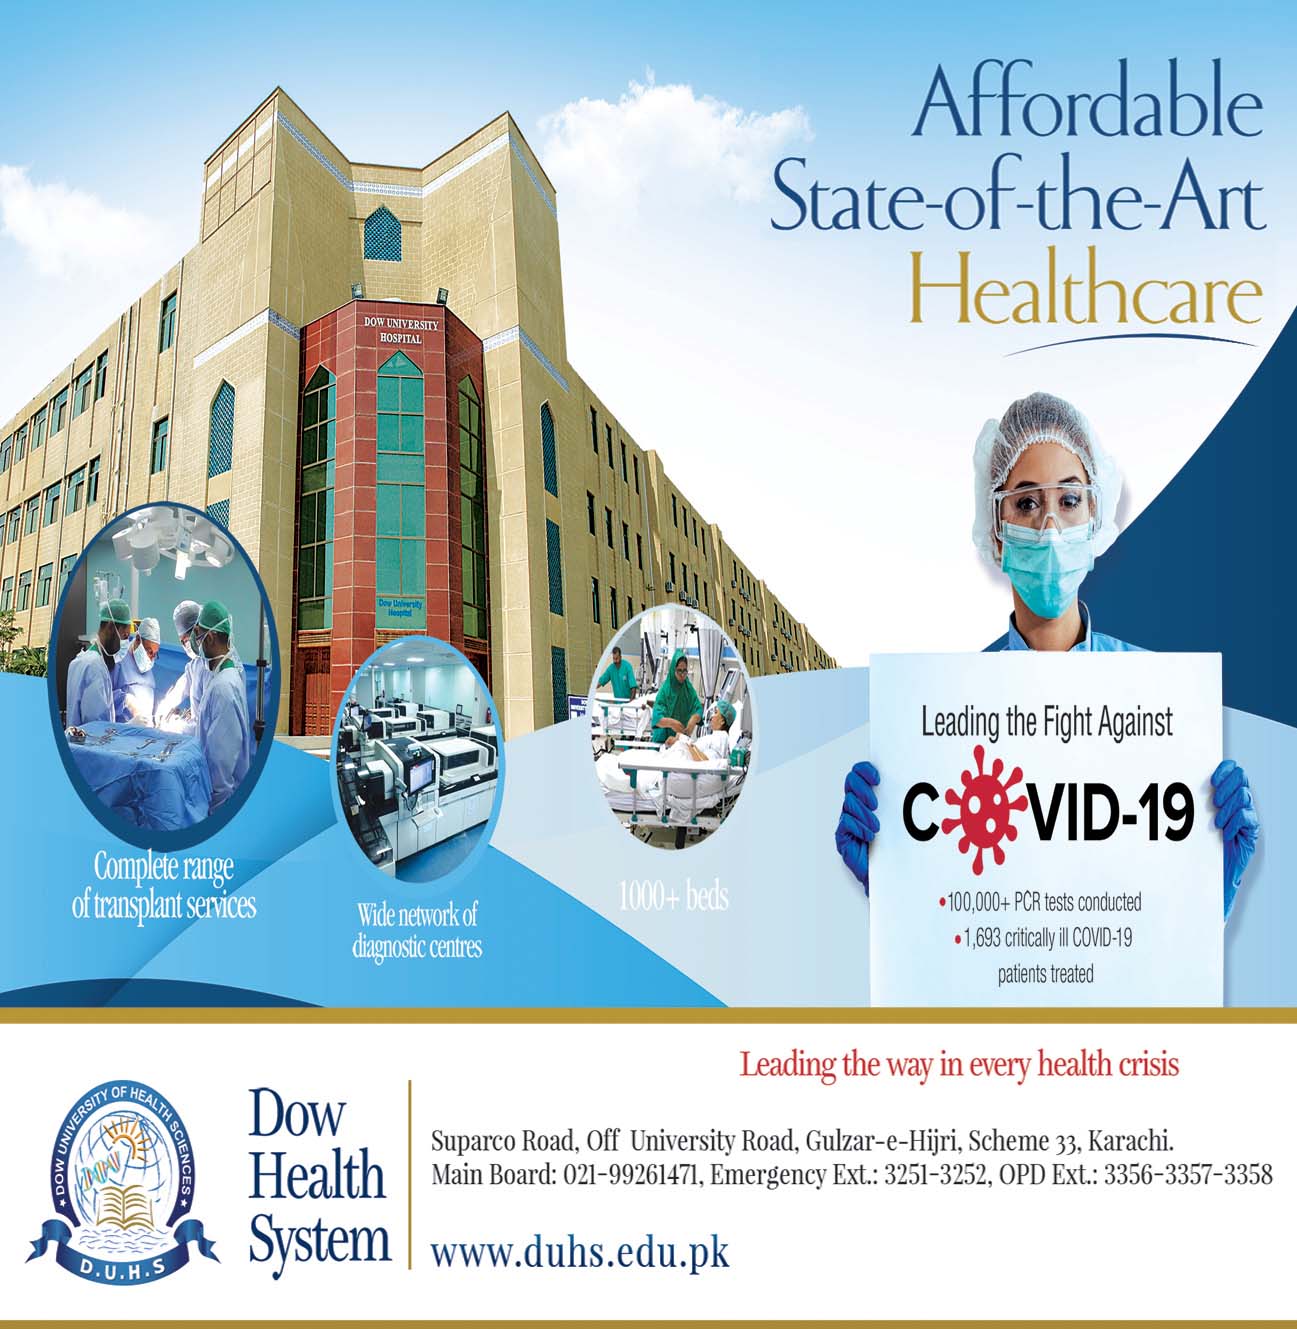

کراچی: ڈاؤ میڈیکل کالج میں ٹیمپورل بون ڈائی سیکشن اسکل لیبارٹری کا افتتاح کردیا گیا، یہ صوبہ سندھ کی سرکاری یونیورسٹی میں ٹیمپورل بون ڈائی سیکشن کی سب سے بڑ ی لیبارٹری ہے جو ڈاؤ میڈیکل کالج میں قائم کی گئی ہے،اس لیبارٹری کو شعبہ اوٹورہینولیرنگولوجی یڈ اینڈ نیک سرجری کا ایک اہم سنگِ میل قرار دیا جارہا ہے، افتتاحی تقریب میں چیئرمین ہائر ایجوکیشن کمیشن سندھ، پروفیسر طارق رفیع نے مہمان خصوصی کی حیثیت سے شرکت کی، ڈاؤ یونیورسٹی آف ہیلتھ سائنسز کے وائس چانسلر پروفیسر محمد سعید قریشی نے بطور مہمان اعزازی جبکہ پرو وائس چانسلر پروفیسر نازلی حسین، پرنسپل ڈاؤ میڈیکل کالج پروفیسر صبا سہیل، برطانیہ سے ڈاکٹر شادابہ احمد، فیکلٹی ممبرز اور پوسٹ گریجویٹ ٹرینیز نے بھی شرکت کی،

افتتاحی تقریب سے خطاب کرتے ہوئے چیئرمین ایچ ای سی سندھ پروفیسر طارق رفیع نے کہاکہ ٹیمپورل بون ڈائی سیکشن، اوٹولیرنگولوجی ٹریننگ کا ایک اہم جز و، جس میں اناٹومیکل علوم اور سرجری میں مہارت کی ضرورت ہوتی ہے، انہوں نے کہا کہ 2000 کی دہائی کی ابتداسے پاکستان میں ا س شعبے میں تیزی سے جدت آئی ہے، جدید تربیتی پروگرامز، ورکشاپس اور کانفرنسز نے پاکستانی اوٹوولیرنگولوجسٹس کی مہارت میں نمایا ں اضافہ کیا ہے،

اس موقع پر ڈاؤ یونیورسٹی کے وائس چانسلر پروفیسر محمد سعید قریشی نے کہا کہ اسکل لیبارٹری کے قیام کے ذریعے ریزیڈینٹس کو سرجری کی صلاحیت کو نکھارنے کے لیے ایک مخصوص جگہ فراہم کی گئی ہے جس کا مقصد اسٹیشنز اور لیبارٹری کو جدید آلات اور بہتر سہولیات سے لیس کرنا،صلاحیتوں بہتر اور مضبوط بنانا ہے، انہوں نے کہا کہ اسکل لیب کے قیام میں ڈاؤ یونیورسٹی کے-ای این ٹی ڈپارٹمنٹ کی چیئرپرسن پروفیسر زیبا احمد اور ان کی ٹیم کی

کوششیں قابل قدر ہیں، لیبارٹری میں 7 اسٹیشنز ہیں جن میں سے 5 مکمل طور پر آپریٹنگ مائیکرواسکوپس سے لیس ہیں، اس لیبارٹری سے، نظریاتی علم اور عملی اطلاق کے مابین فرق کو ختم کرنے میں مدد ملے گی تاکہ ٹرینیز ضروری سرجیکل مہارت حاصل کر سکیں اور مریضوں کو بھی بہترین سہولیات فراہم کی جاسکیں، اس لیبارٹری سے ٹیمپورل بون کی ڈائیسیکشن اور سرجری کی ہینڈز آن ٹریننگ، ٹیمپورل بون کی اناٹومی کو سمجھنے میں مدد ملے گی، سرجری کو سمجھنے اور اہم ترین اعضا کو پہچاننے اور انہیں محفوظ کرنے کی صلاحیت میں اضافہ ہوگا۔